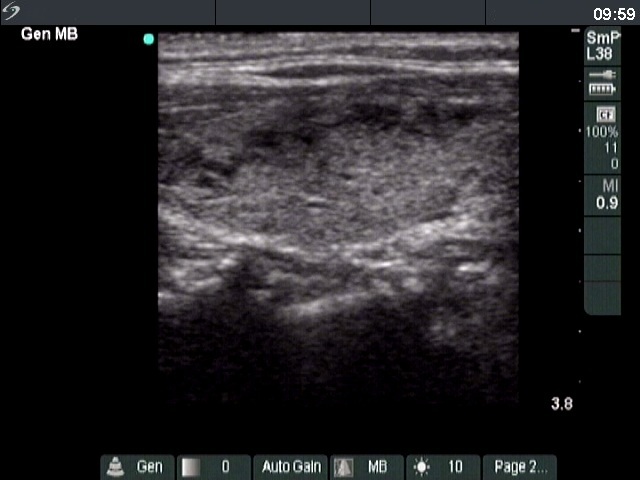

Ultrasonography. The thyroid was echonormal and presented several hypoechoic areas. The pattern in the right lobe was obviously focal form of lymphocytic thyroiditis.

A relatively large hypoechoic areas was found in the left lobe. The lesion had irregular borders. At first sight, this presentation of the left lobe could be interpreted as the central hypoechoic area-type form of lymphocytic thyroiditis. However, the hypoechoic lesion was not entirely surrounded with echonormal thyroid tissue. More importantly, the central hypoechoic areas-type form is almost always bilateral.

The sonographic pattern is remarkable. On the one hand, the tumor was identical to other more active foci of Hashimoto's thyroiditis. The only difference was the size of this lesion which was larger than other lesions observed in the thyroid. In the case of Hashimoto's thyroiditis neither the irregularity of border, nor the increased vascularization has any relevance. On the other hand, the tumor had microcalcifications and was significantly larger than other foci. The lesson to draw is the comparison of various lesions: if we detect a lesion which differs from others regarding the echogenicity, the size or the vascularization, it is advisable to perform FNA.